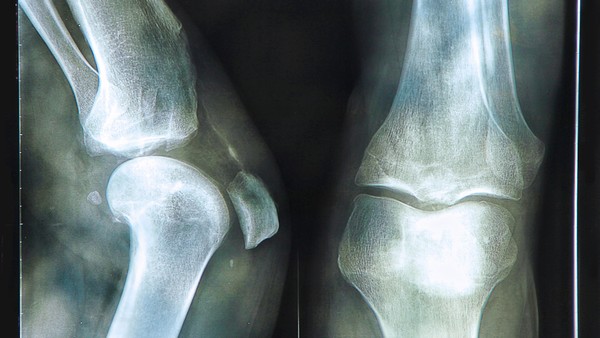

骨关节炎(Osteoarthritis, OA)是最常见的关节疾病之一,主要由关节软骨的退化和磨损引起,通常伴随骨骼增生和炎症反应。随着年龄的增长,骨关节炎的发病率逐渐增加,其主要症状包括关节疼痛、僵硬和功能障碍。在探讨骨关节炎的疼痛是否会持续时,需要考虑多种因素,包括个体差异、病情进展及治疗措施。

骨关节炎的疼痛通常呈现为间歇性或持续性。早期阶段的患者可能只在活动后感到疼痛,而休息时症状减轻。随着病情的加重,疼痛可能变得更加频繁并逐渐转为持续性,特别是在夜间或静止状态下。这种情况下,疼痛不仅影响生活质量,还可能导致心理健康问题,如焦虑和抑郁。